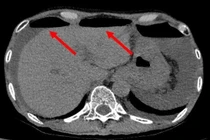

(khoahocdoisong.vn) - Chảy máu do loét dạ dày tá tràng là một cấp cứu thường gặp chiếm 40 – 45% trong chảy máu đường tiêu hóa trên. Bệnh hay gặp ở bệnh nhân trên 50 tuổi, có tiền sử loét dạ dày tá tràng nhiều năm, chảy máu nhiều lần gặp nhiều ở những bệnh nhân có nhóm máu O...